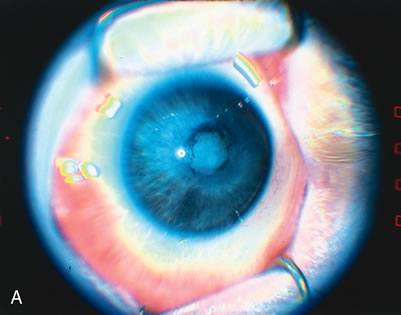

threshold retinopathy of prematurity. Arch Ophthalmol 119:615, 2001 51. Rundle P, McGinnity FG: Bilateral hyphaema following diode laser for retinopathy of prematurity. Br J Ophthalmol 79:1055, 1995 52. Simons BD, Wilson MC, Hertle RW, Schaefer DB: Bilateral hyphemas and cataracts after diode laser retinal photoablation

for retinopathy of prematurity. J Pediatr Ophthalmol Strabismus 35:185, 1998 53. Capone A Jr, Drack AV: Transient lens changes after diode laser retinal photoablation for retinopathy

of prematurity. Am J Ophthalmol 118:533, 1994 54. Drack AV, Burke JP, Pulido JS, Keech RV: Transient punctate lenticular opacities as a complication of argon laser

photoablation in an infant with retinopathy of prematurity. Am J Ophthalmol 113:583, 1992 55. Pogrebniak AE, Bolling JP, Stewart MW: Argon laser-induced cataract in an infant with retinopathy of prematurity. Am J Ophthalmol 117:261, 1994 56. Lambert SR, Capone A Jr, Cingle KA, Drack AV: Cataract and phthisis bulbi after laser photoablation for threshold retinopathy

of prematurity. Am J Ophthalmol 129:585, 2000. 57. Noonan CP, Clark DI: Acute serous detachment with argon laser photocoagulation in retinopathy

of prematurity. J Aapos 1:183, 1997 58. Algawi K, Goggin M, O'Keefe M: Refractive outcome following diode laser versus cryotherapy for eyes with